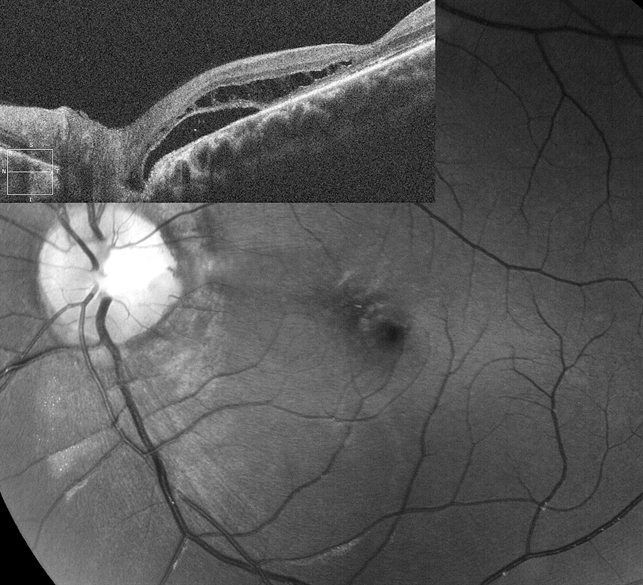

- формируется ретиношизис внутренних слоев сетчатки, полость которого сообщается непосредственно с ямкой диска

- образуется разрыв наружных слоев сетчатки ниже границ полости ретиношизиса;

- отслойка наружных слоев развивается вокруг макулярного разрыва, что связано с притоком жидкости из полости ретиношизиса (отслойка наружных слоев сетчатки при офтальмоскопии может имитировать отслойку пигментного эпителия, но при ФАГ не отмечается характерной для последней гиперфлюоресценции);

Отслойка наружных слоев в конечном итоге увеличивается и облитерирует полость ретиношизиса. На этой стадии осложнение клинически неотличимо от первичной серозной макулярной отслойки.

На ангиографии ямка диска выглядит как зона гипофлюоресценции в раннюю и промежуточную фазу. У большинства пациентов отмечается ее гиперфлюоресценция в позднюю фазу. Диффузия красителя за пределы ямки, в область серозной отслойки сетчатки обычно отсутствует.

Гистологически ямка диска зрительного нерва представляет собой грыжевидное выпячивание элементов нейросенсорной сетчатки в области дефекта решетчатой пластинки склеры. Ретинальные волокна опускаются внутрь ямки, затем возвращаются и выходят перед входящим зрительным нервом. Некоторые ямки сообщаются с субарахноидальным пространством.

Возникновение отслойки сетчатки связывают с пассажем внутриглазной жидкости под сетчатку в области ямки зрительного нерва или проникновением ликвора из субарахноидального пространства по межоболочечным пространствам зрительного нерва.